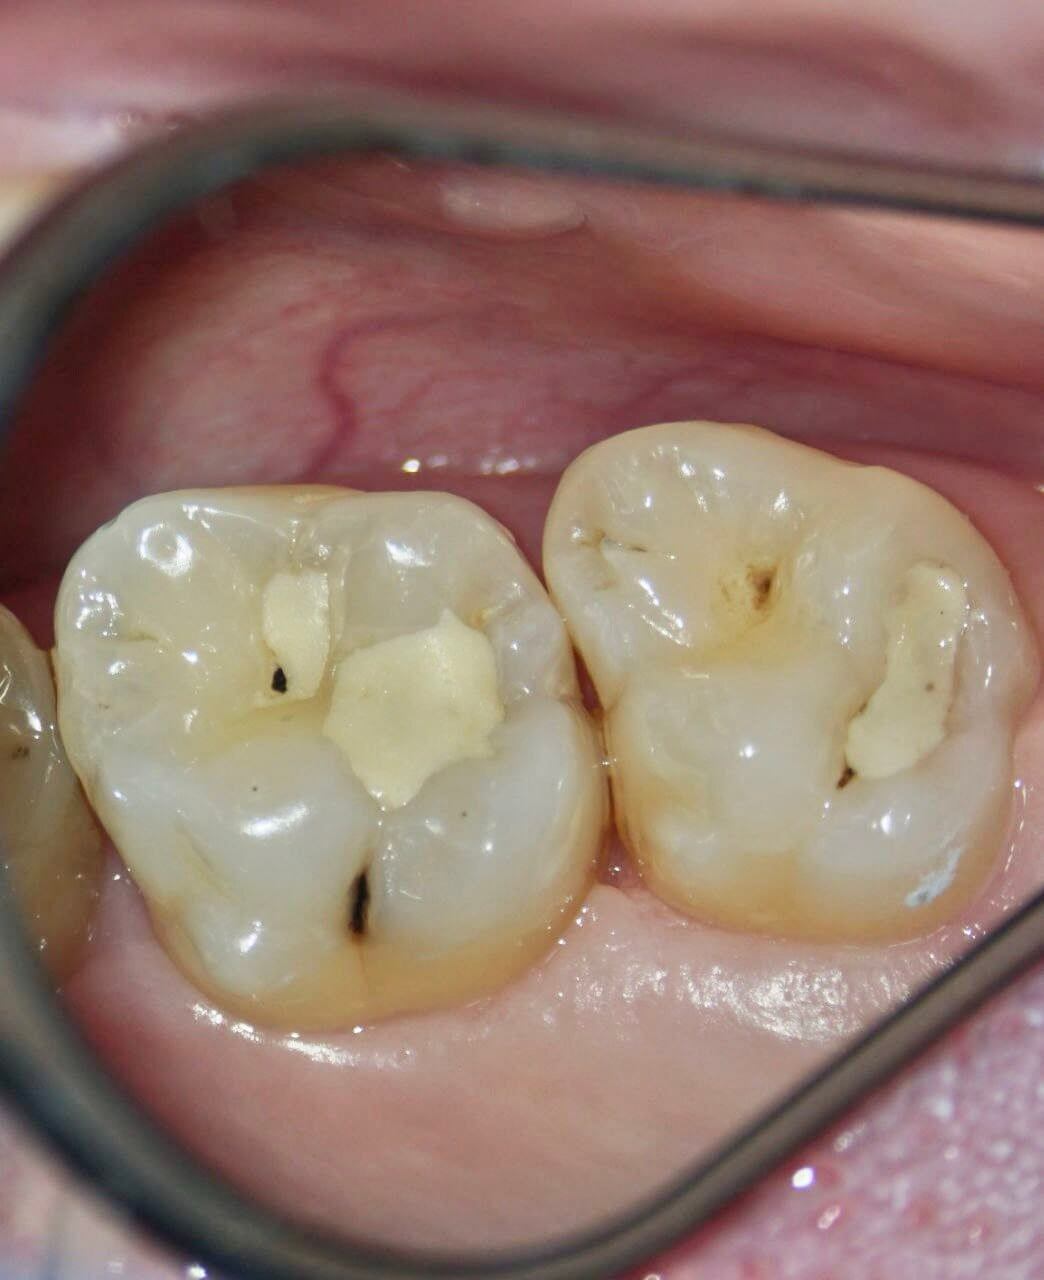

Цель визита: восстановление жевательных поверхностей зубов после окончания 3 лет ортодонтического лечения. + жалобы на застревание пищи между зубами (17 имеет вогнутость, сформированная до ортодонтии из-за неправильного положения зуба) и кровоточивость из десневого сосочка.